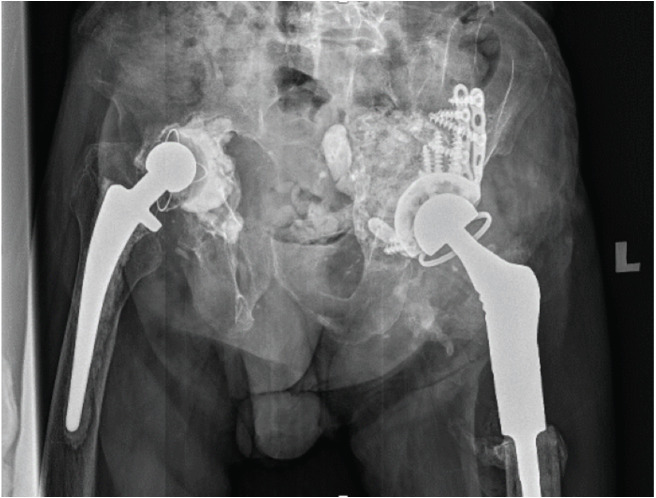

全髋关节置换术(THA)翻修手术中骨丢失的修复具有挑战性。髋臼嵌塞骨移植(AIBG)可以恢复骨存量和正常的髋关节生物力学。AIBG通常作为髋关节假体植入的单阶段手术进行,因为传统上认为,足够的阻生移植物负荷对于与宿主骨融合是必要的,从而防止骨吸收。我们提出一个73岁的绅士谁提出了双侧髋关节疼痛和减少活动。他被诊断为左侧THA无菌性松动伴髋臼突出,随后使用辐照的同种异体股骨头移植物进行了两期AIBG。第一阶段在没有髋臼负荷的情况下进行,但同种异体移植物成功地与宿主骨结合。这是首次报道的两期AIBG病例,表明同种异体移植物与宿主骨融合可能不需要髋臼负荷。因此,必要时,AIBG可以分两阶段进行,特别是在复杂的髋关节翻修手术和骨存量差的患者中。

Restoring bone loss in revision Total Hip Arthroplasty (THA) surgery is challenging. Acetabular impaction bone grafting (AIBG) allows the restoration of bone stock and normal hip biomechanics. AIBG is usually performed as a single-stage surgery with hip component implantation, as it is traditionally believed that adequate loading of the impacted graft is necessary for integration with the host bone thus preventing bone resorption. We present a case of a 73-year-old gentleman who presented with bilateral hip pain and reduced mobility. He was diagnosed with left THA aseptic loosening with acetabular protrusion and subsequently underwent a two-stage AIBG using irradiated femoral head allografts. The first stage was performed without acetabular loading, yet the allograft successfully integrated with the host bone. This is the first reported case of a two-stage AIBG demonstrating that acetabular loading may not be required for allograft integration to host bone. Therefore, AIBG may be performed as a two-stage procedure, when necessary, especially in the setting of complex revision hip surgeries and patients with poor bone stock.